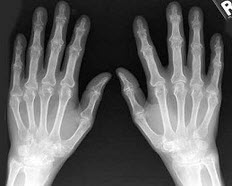

3、单项选择题

男,45岁,双足肿痛,晨僵,结合图像,最可能的诊断是()

A.关节结核

B.痛风性关节炎

C.类风湿关节炎

D.牛皮癣性关节炎

E.Reiter综合征

B.X线胸片呈多发边缘锐利、密度均匀高密度影

女,45岁,结合图像,最可能的诊断是()

A.类风湿关节炎

B.痛风

C.假痛风

E.神经性关节病